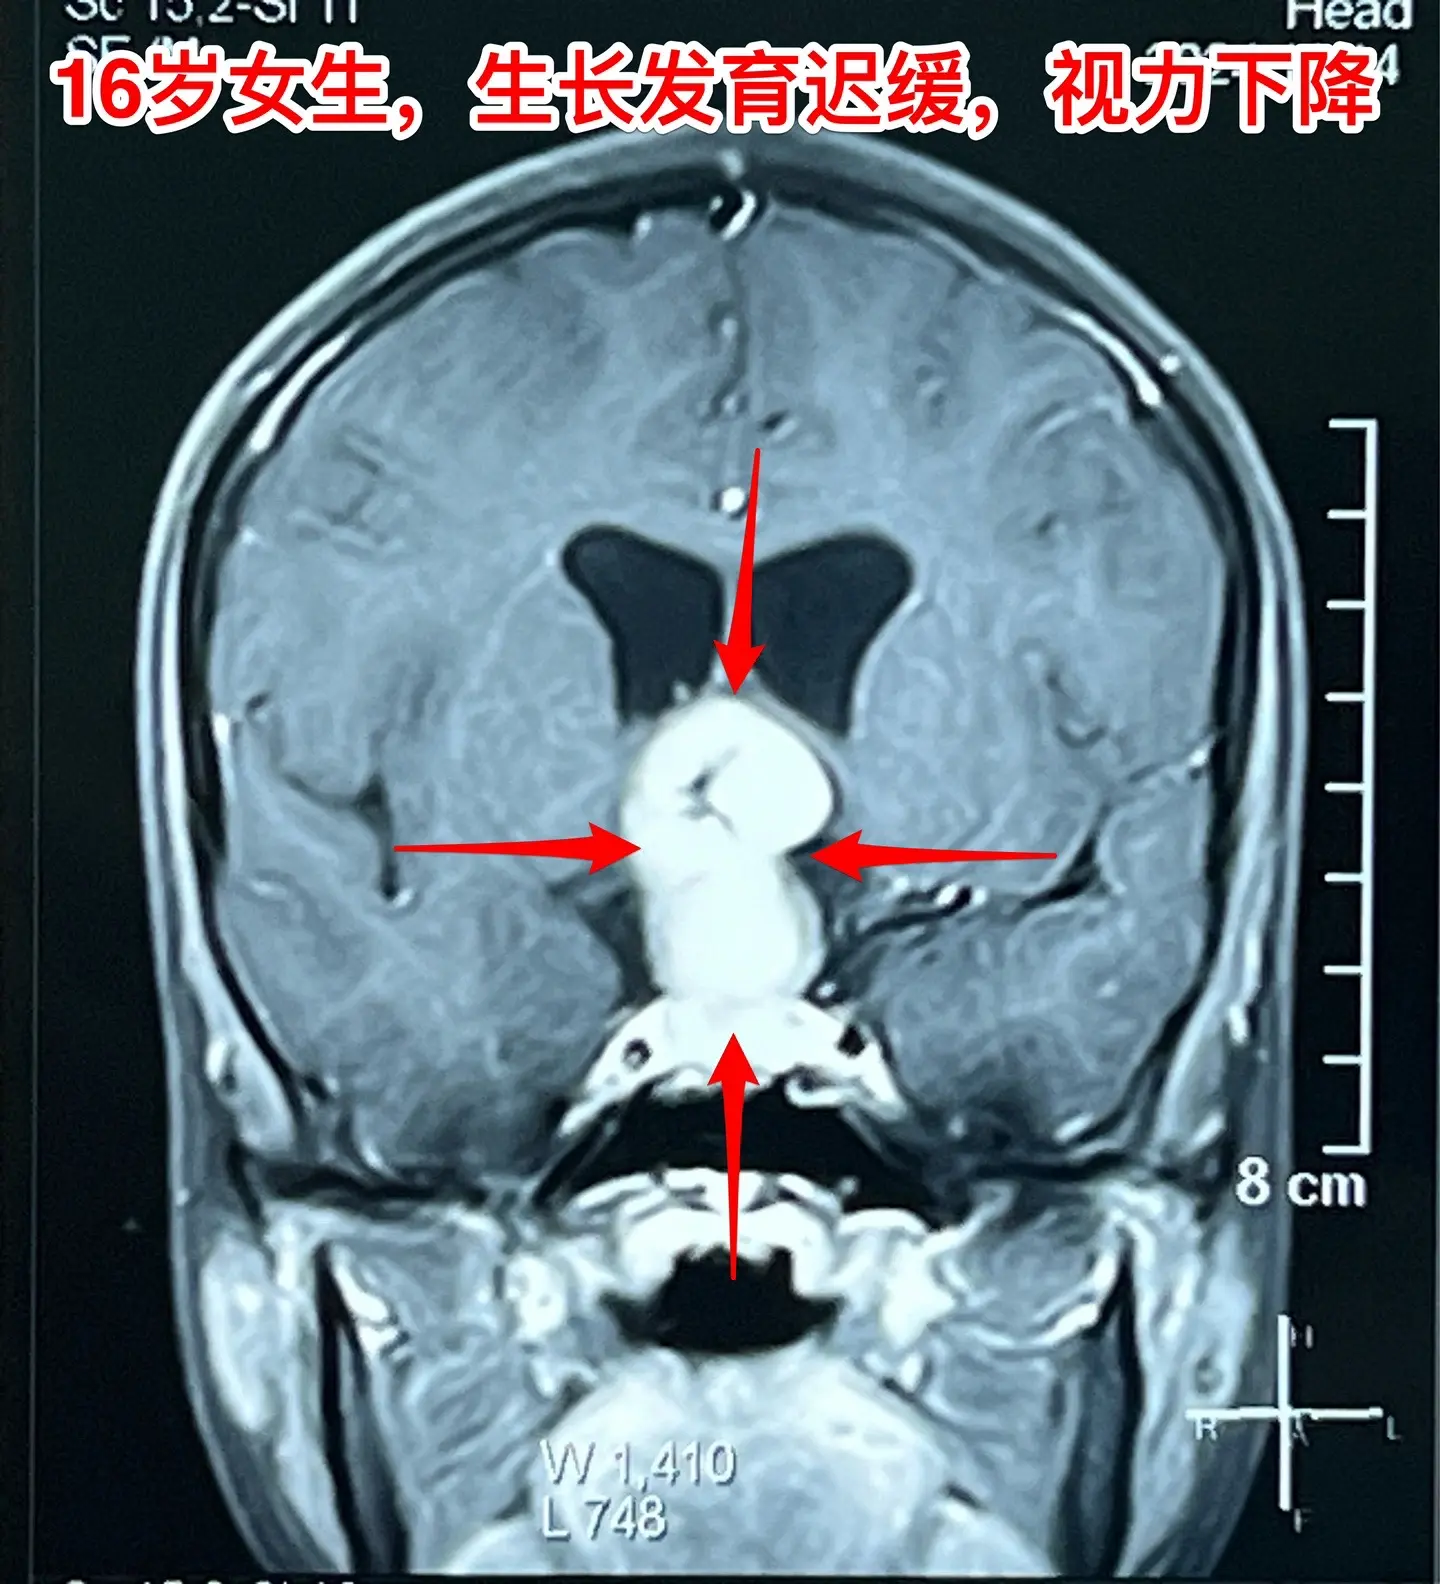

16岁女生在10岁时就有生长发育迟缓症状。16岁衡阳市女生,现在身高才120厘米,体重才21公斤。初中毕业后就辍学了! 她在10岁时就有生长发育迟缓症状,到医院去检查发现生长激素分泌不足。没有找出具体原因,也没有注射生长激素治疗。 近一年有头痛症状,视力也下降了。作磁共振发现长了脑部肿瘤,才到北京来找我作手术。肿瘤体积大,没有钙化,是颅咽管瘤吗? 昨天在手术过程中,取出病变标本作快速冰冻病理检查,报告为乳头型颅咽管瘤。这种类型的颅咽管瘤在小孩子中十分罕见。 我多次提醒家长,如果发现小孩子的生长发育有异常,要尽早到医院去检查,找出原因,尤其是针对脑部要作磁共振检查,排除脑部肿瘤。对于生长激素缺乏者,不能不管原因,轻易注射生长激素治疗。